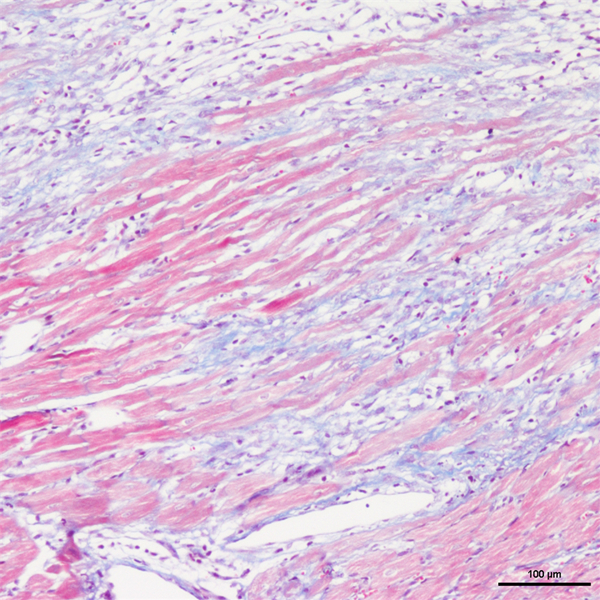

Masson染色

丽春红酸性品红-苯胺蓝染色,是用于检测动物组织中胶原纤维的一种染色方法之一,能够将胶原纤维染成蓝色,肌纤维、和红细胞呈红色,可用于鉴胶原纤维和肌纤维;并显示各种组织胶原纤维含量及纤维化程度。

Masson染色时胶原纤维呈蓝色(被苯胺蓝所染)或绿色(被亮绿所染),肌纤维呈红色(被酸性品红和丽春红所染),这与阴离子染料分子的大小和组织的渗透性有关。如已固定的组织用一系列阴离子水溶性染料先后或混合染色,则可发现红细胞被最小分子的阴离子染料着染,肌纤维与胞质被中等大小的阴离子染料着染,而胶原纤维则被大分子的阴离子染料着染。由此说明了红细胞对阴离子染料的渗透性最小,肌纤维与胞质次之,而胶原纤维具有最大的渗透性。根据组织不同的渗透性能,选择分子大小不同的阴离子染料进行染色,便可把不同组织成分显示出来。